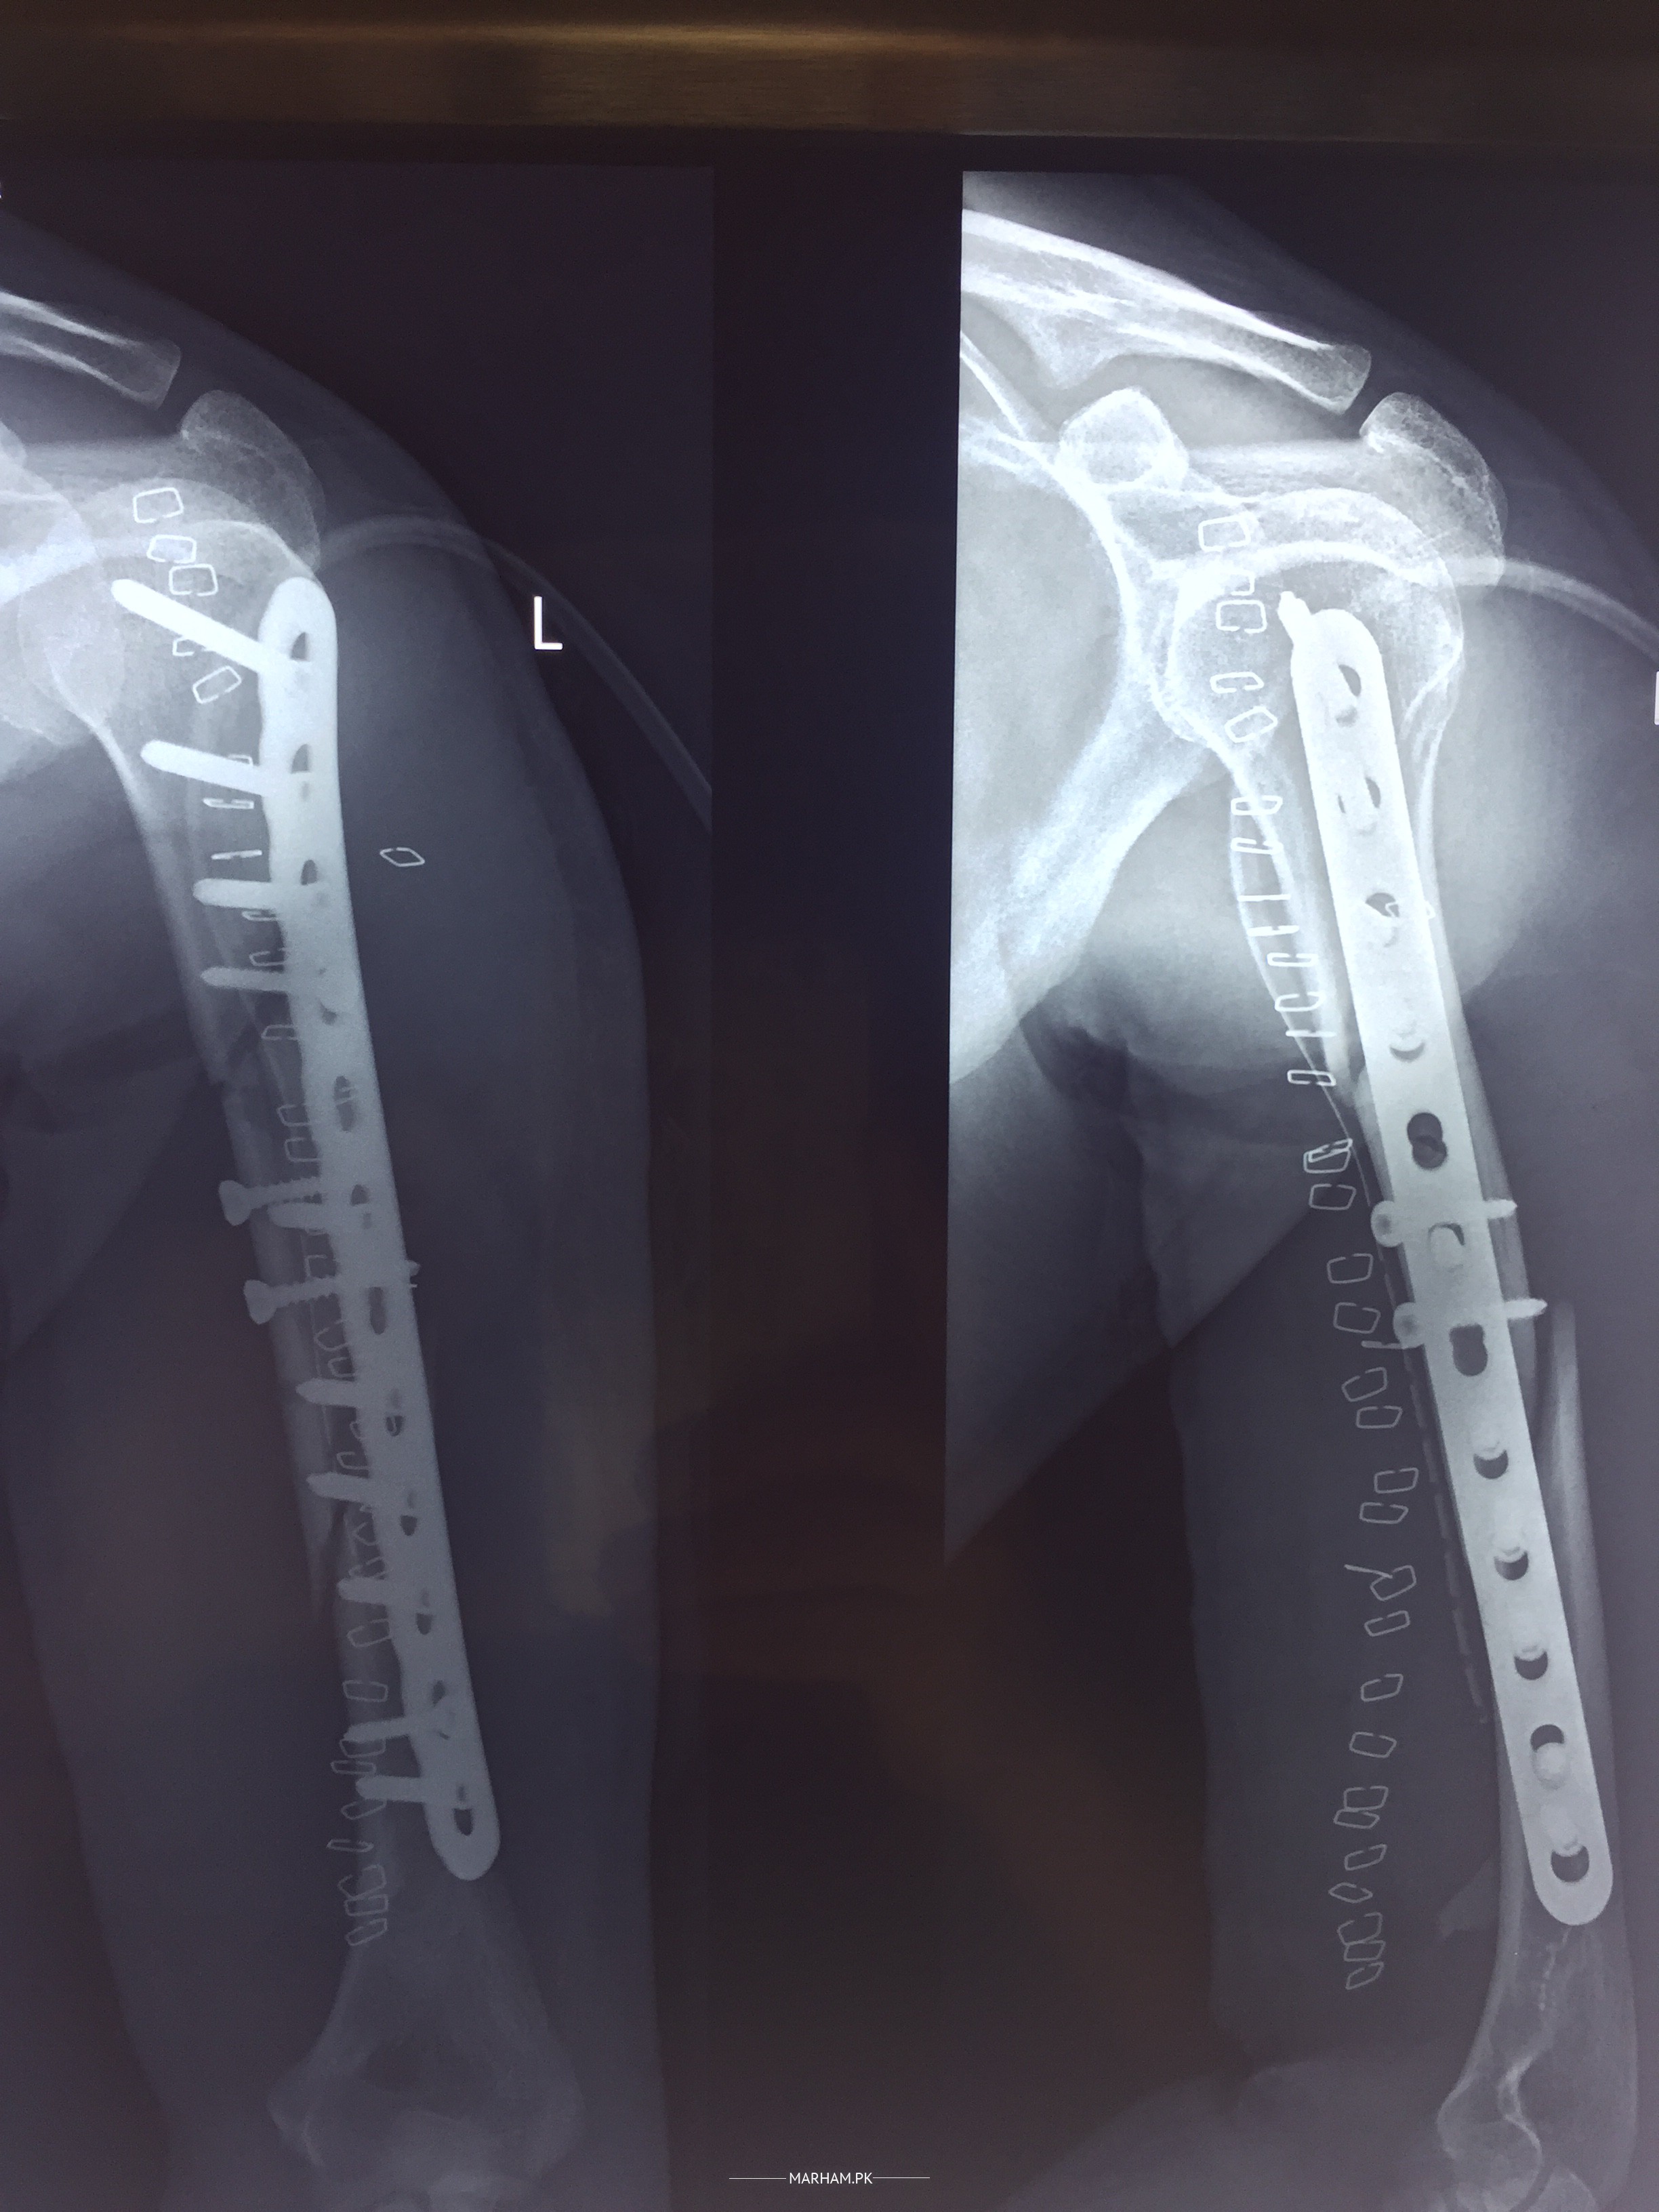

Attached are the pre surgery and post surgery X-ray images. is every thing fine

xrays are looking fine.